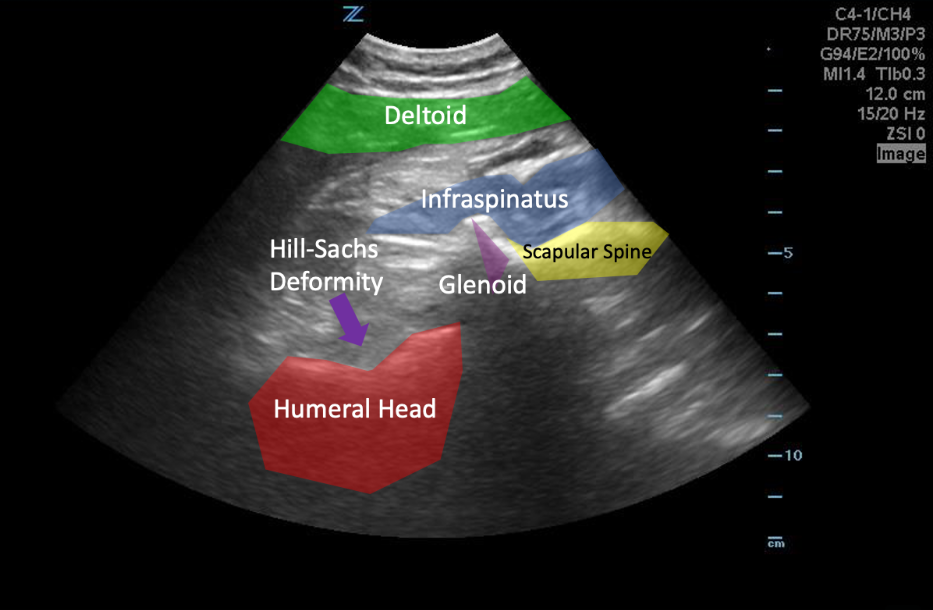

A 55-year-old female presents after a fall at home. She is complaining of new shoulder pain and holding her arm in an abducted and externally rotated position. You grab your ultrasound for a quick, noninvasive (and sensitive!) evaluation and see the following:

Image 4: Author's own image